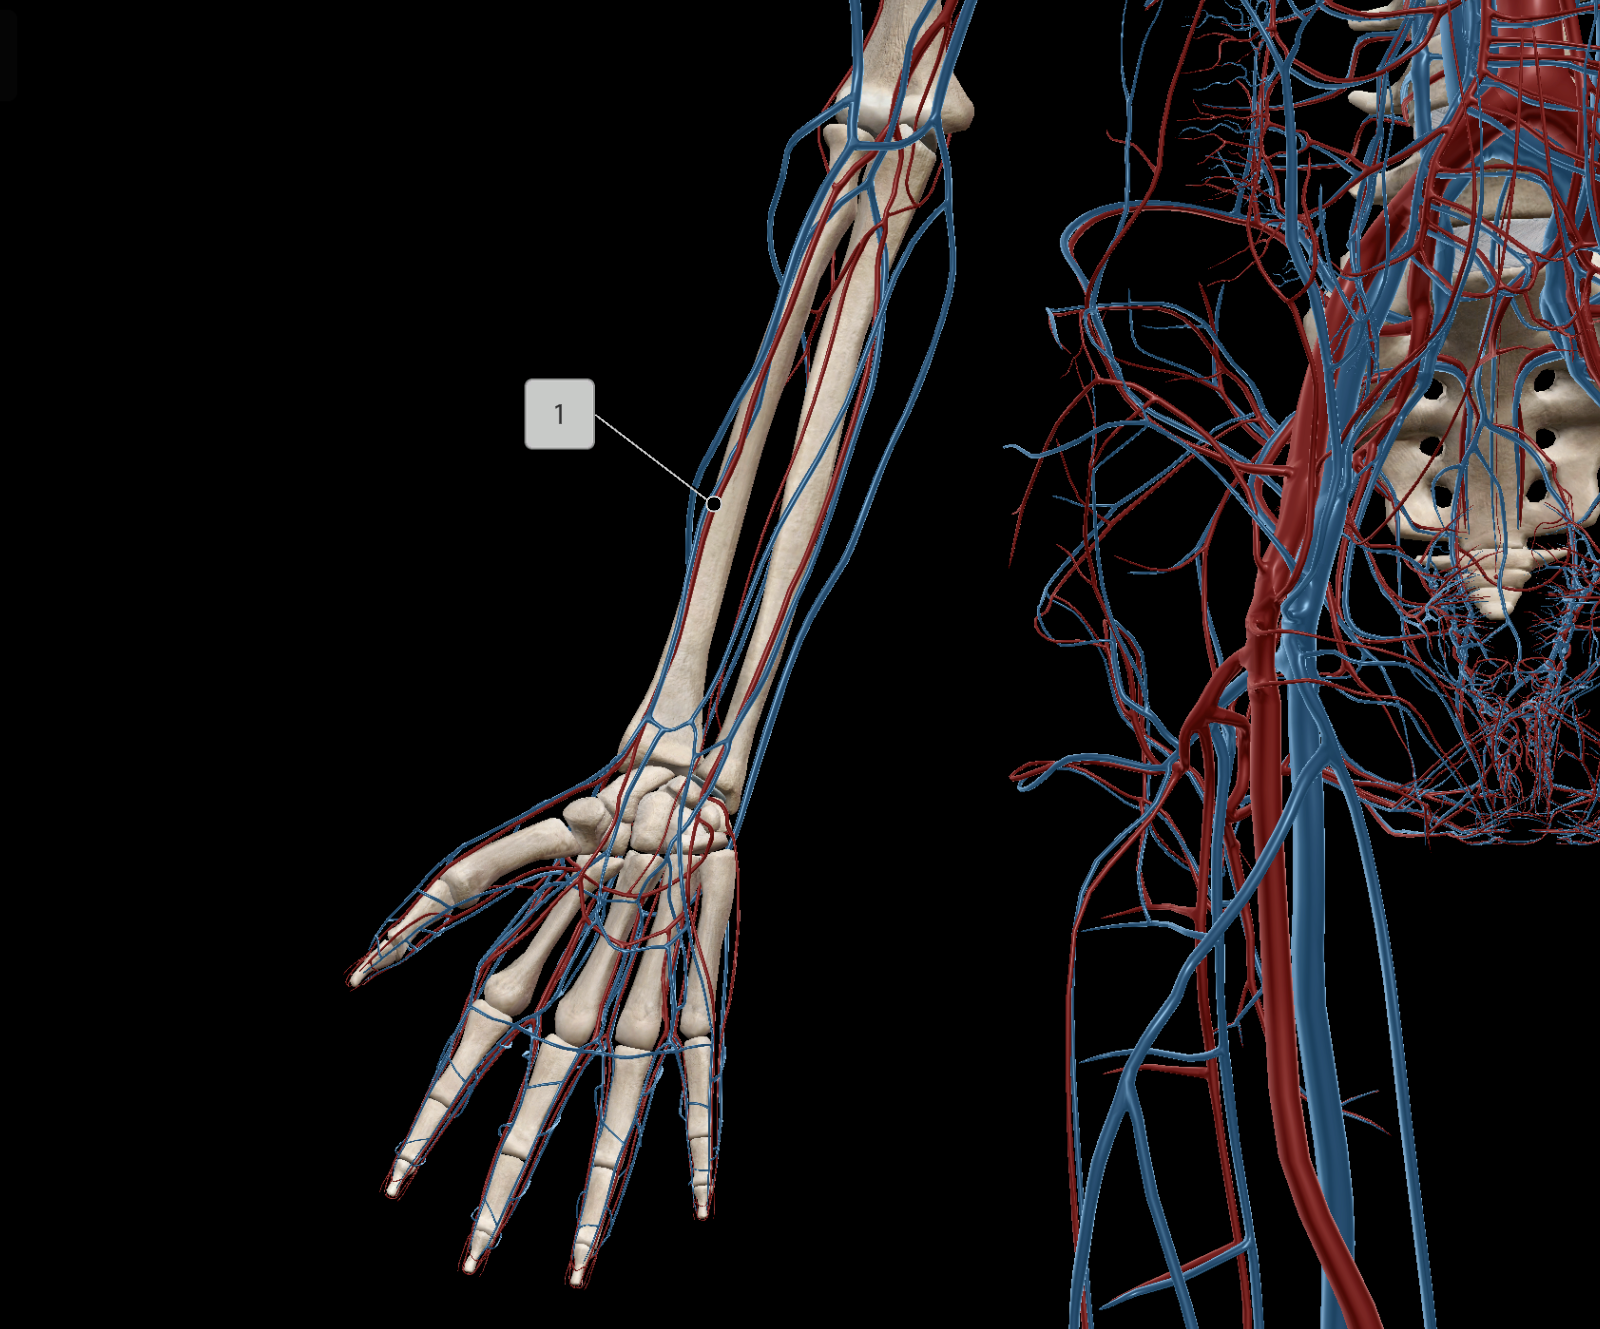

Brachial Artery

Ulnar Artery

Radial Artery

Brachial Vein

Radial Vein

Ulnar Vein